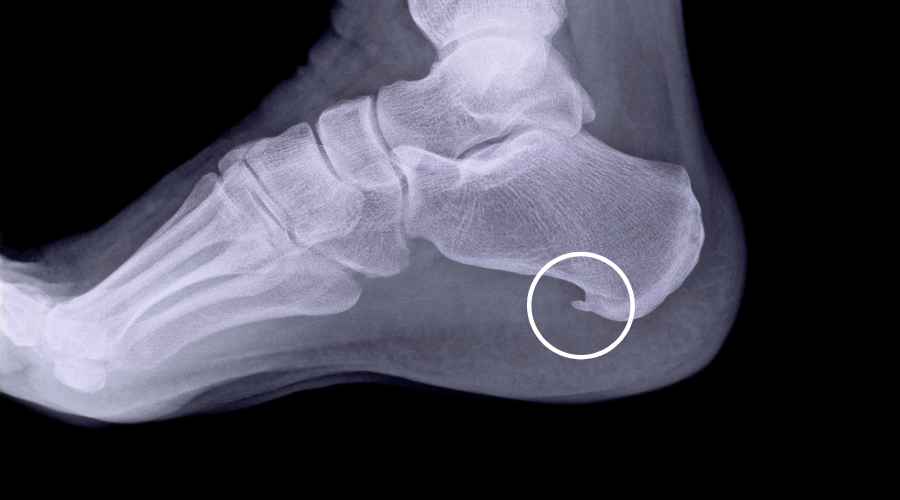

Il piede piatto è determinato da una riduzione di altezza dell’arco longitudinale mediale, che si forma tra il calcagno e il primo osso metatarsale.

Eccolo in questa foto!

Quando avviene il “collasso” di questo arco, la parte interna (o mediale) del piede si appiattisce e il piede si avvicina al suolo, fino anche a toccare a terra.